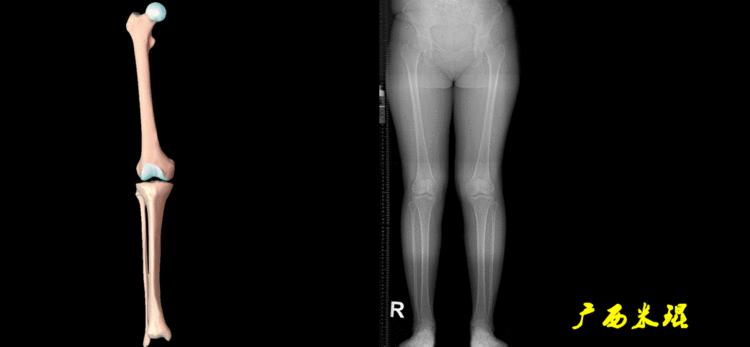

下肢力线及相关角度测量的前提是必须拍摄标准的站立位也就是负重位的下肢全长片。目前这样的照片都是放射科的技师在电脑上拼接出来的,大部分医院的DR都能够做到这一点。

无论如何,拍摄出来的下肢全长片必须包含髋关节中心、膝关节中心及踝关节中心,否则对临床是无用的。有了一张下肢的全长照片,我们需要确定下肢关节的中心点,通过中心点画出下肢的各种轴线,然后利用轴线与关节线的相交得出各种所需要的角度。

1、确定下肢关节的中心点

(1)髋关节中心

髋关节中心点由股骨头来确定,由于股骨头是相对比较规则的圆形,使用Mose圈或圆规就能确定股骨头中心也就是髋关节中心。

(2)膝关节中心

膝关节中心点常用的有5个不同的定位方法,分别是股骨髁中点、股骨髁间窝顶点、膝关节间隙水平软组织中点、胫骨髁间嵴中点和胫骨平台中点,我们可以根据具体情况来选用。

(3)踝关节中心

踝关节中心点常用的也有3个,分别是骨骼(内、外踝表面间距)中点、踝关节间隙水平软组织中点和距骨宽度中点。

2、画出下肢的轴线

确定髋关节、膝关节、踝关节的中心点后,我们才能了解下肢的几个轴线。